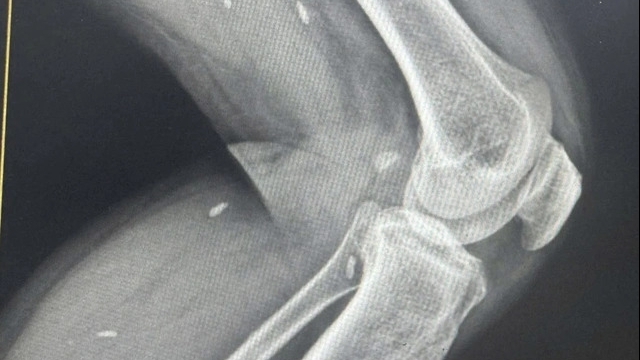

Một tuần trước vào viện, bệnh nhân xuất hiện nhọt ở cánh mũi và có dấu hiệu hoại tử lan rộng, đồng thời xuất hiện thêm ổ áp-xe ở khớp cổ chân phải.